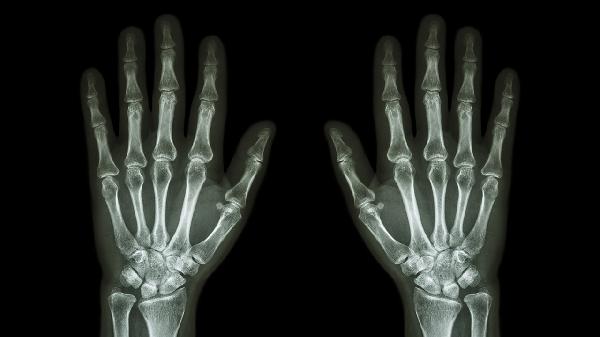

病理性骨折通常表现为局部疼痛、肿胀、活动受限,可能由骨质疏松、骨肿瘤、骨髓炎、骨代谢异常、长期激素治疗等因素引起。